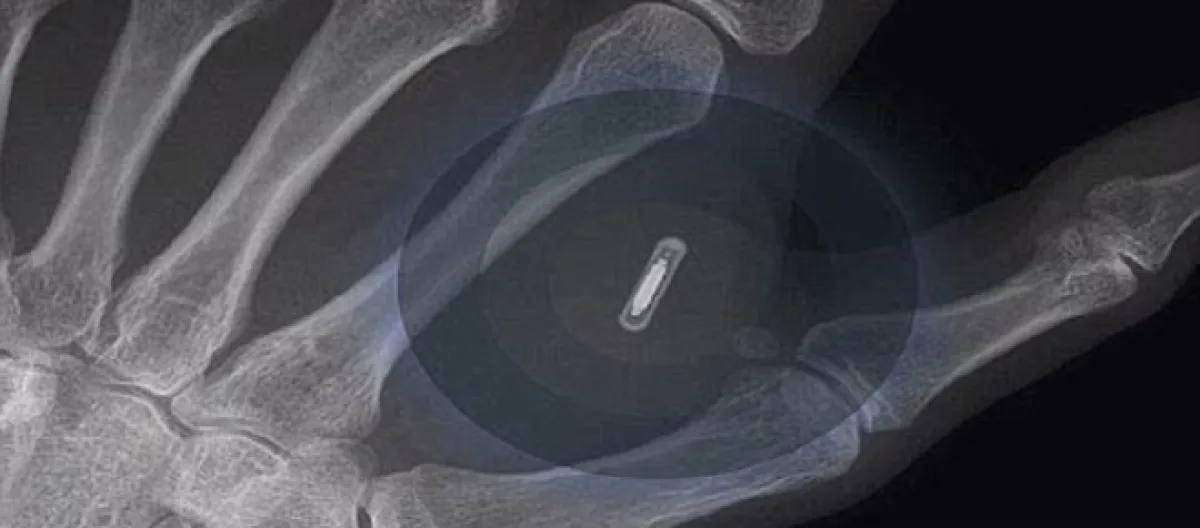

Three Square Market CEO Todd Westby said the technology would eventually become standardized that authorities would allow it to be used as a passport, to ride public transit, and for various purchases. The New York Post reported that chip is implanted between the thumb and the forefinger within seconds.

An inaugural chip party will be held on Aug. 1 at the headquarters of Three Square Market on Aug. 1. The microchip, which is as small as a grain of rice, will be used similarly to how people use their mobile phone to purchase goods.

It takes a few seconds to implant the chip, and the procedure is usually painless, Jowan Osterland, CEO of BioHax International, said. Three Square Market had partnered with BioHax which will perform the procedure.